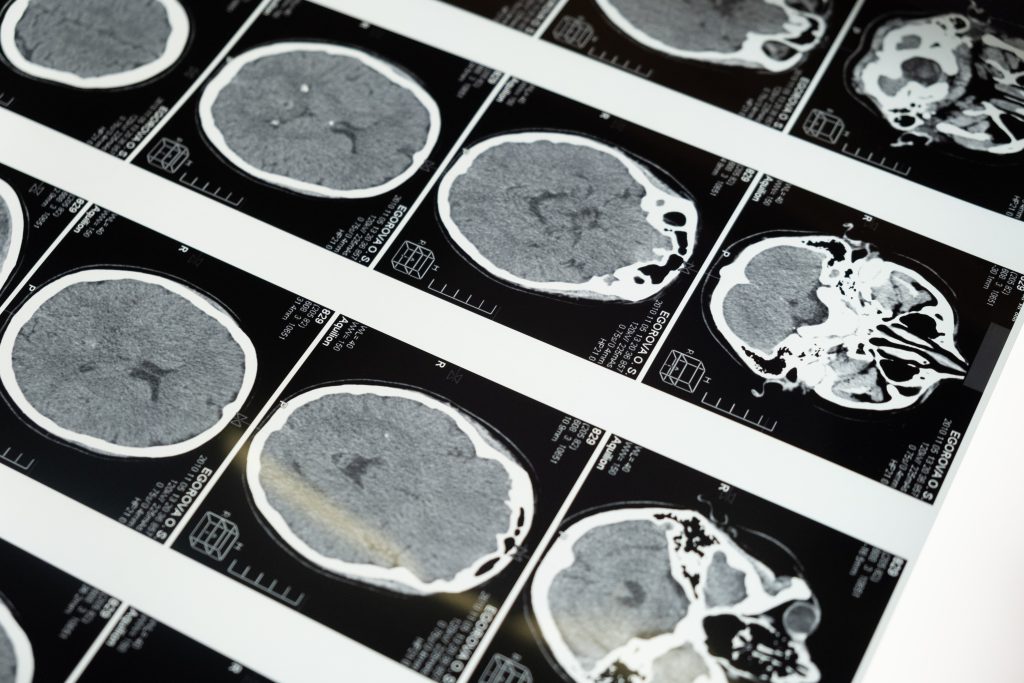

Rezonans magnetyczny jest jednym z najważniejszych badań diagnostycznych, które pozwala uzyskać szczegółowe obrazy wnętrza ciała. Często pacjenci, którzy przeszli to badanie, zastanawiają się, jak długo będą musieli czekać na wynik i jak go zinterpretować. W tym artykule omówimy te kwestie, aby dostarczyć Tobie pełnej wiedzy na temat rezultatów rezonansu magnetycznego.

Interpretacja wyników rezonansu magnetycznego może być skomplikowana dla osób niezaznajomionych z medycznymi terminami. Wynik badania jest zazwyczaj opisany w fachowym języku, który może być trudny do zrozumienia dla przeciętnego pacjenta. Warto jednak pamiętać, że wyniki są dostosowane do konkretnej sytuacji i zawsze powinny być omówione z lekarzem. Dzięki rezonansowi magnetycznemu można zdiagnozować wiele różnych stanów, takich jak nowotwory, guzy, zmiany zapalne czy choroby serca. Jednak dokładne znaczenie wyników zawsze zależy od kontekstu medycznego i dotychczasowego stanu zdrowia pacjenta.